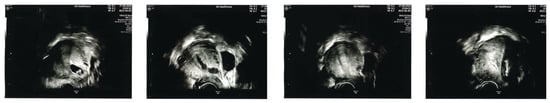

- If surgical management is performed, intraoperative transrectal ultrasound guidance is crucial to reduce the risk of retained tissue, bleeding and uterine perforation. Post operative intrauterine haematoma is common and can be difficult to differentiate from retained products of conception. Therefore, objective sonographic evidence of complete uterine evacuation at the time of the procedure improves postoperative investigation and diagnosis.